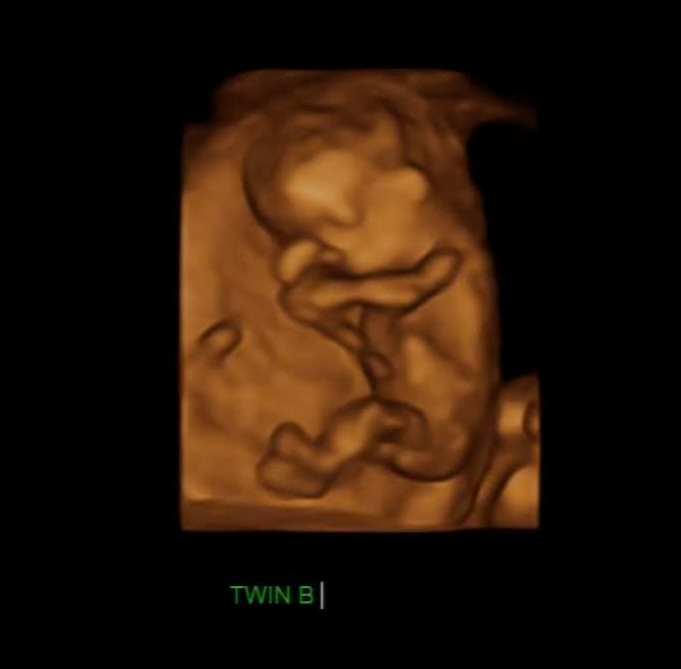

임신 16 ~ 20주가 되면 산모는 처음으로 태동을 느끼는데 이는 태아가 존재함을 표시하는 것이다. 이때 부모들은 태아의 움직임을 느끼면서 아이를 상상해 보게 된다.

저도 쌍둥이들이 뱃속에 있을 때 두 아이의 태동 차이가 컸습니다. 한 녀석은 정말 활발히 움직였고 한 녀석은 거의 움직이지 않았는데요.

한 번은 어쩌다가 의도치 않게 앞으로 넘어지게 됐는데 순간적으로 손으로 배를 가리긴 했지만 배 부분으로 정확히 떨어졌습니다. 그러고 나서 태동이 느껴지지 않는 겁니다 너무 걱정을 했고 바로 병원을 가야 하나 고민을 했는데요. 만약에 그 상황에서 안 좋았다면 양수가 터지거나 배에 통증이 오거나 다른 이상이 생겼을 텐데 딱히 그렇지는 않았습니다. 그렇게 한 10분쯤 지났을 때 갑자기 뱃속에서 꿀렁하는 겁니다. ㅎㅎㅎ 우와 그때의 쫀쫀한 마음은 정말 잊을 수가 없습니다. 움직여 주는 고마운지요. 그런데 한 녀석은 잘 움직이지 않는 것처럼 느껴지는 거예요. 그렇게 5분이 더 지난 후에야 한 녀석이 또 움직였습니다.

태동이 느껴지지 않는다면 마음이 불안해지는 게 사실입니다. 그럴 땐 마음이 불안해서 계속 신경 쓰느니 그냥 병원으로 가는 것을 많이 추천하시더라고요. 저도 한 30분 동안 기다려 봤는데 아무 반응이 없었다면 바로 병원에 갔을 것 같아요.